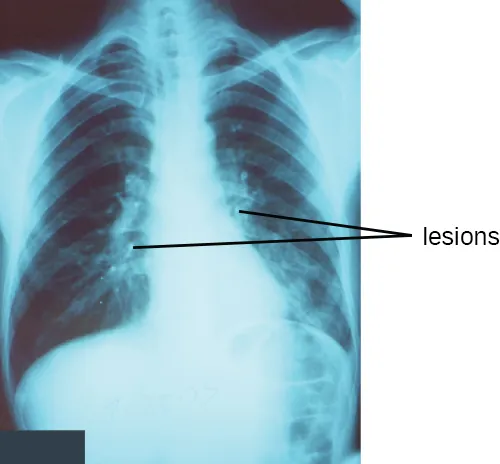

Pneumonia is a general term for infections of the lungs that lead to inflammation and accumulation of fluids and white blood cells in the alveoli. Pneumonia can be caused by bacteria, viruses, fungi, and other organisms, although the vast majority of pneumonias are bacterial in origin. Bacterial pneumonia is a prevalent, potentially serious infection; it caused more 50,000 deaths in the United States in 2014.6 As the alveoli fill with fluids and white blood cells (consolidation), air exchange becomes impaired and patients experience respiratory distress (Figure 22.9). In addition, pneumonia can lead to pleurisy, an infection of the pleural membrane surrounding the lungs, which can make breathing very painful. Although many different bacteria can cause pneumonia under the right circumstances, three bacterial species cause most clinical cases: Streptococcus pneumoniae, H. influenzae, and Mycoplasma pneumoniae. In addition to these, we will also examine some of the less common causes of pneumonia.

An X-ray that shows white bones on a black background. White regions within the lungs are labeled lesions.

Figure 22.9 A chest radiograph of a patient with pneumonia shows the consolidations (lesions) present as opaque patches. (credit: modification of work by Centers for Disease Control and Prevention)